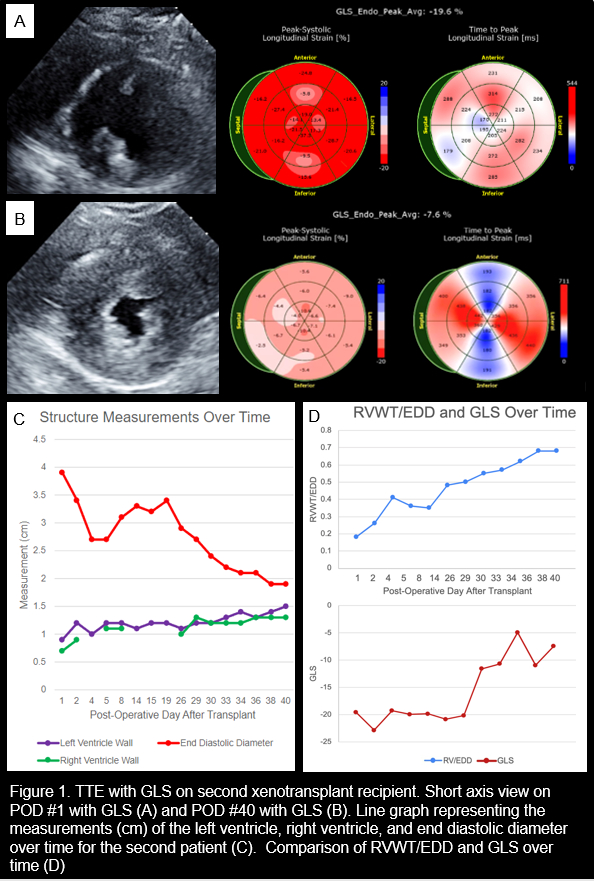

Our institution performed the first two genetically modified porcine cardiac xenotransplantation in humans, conducting serial longitudinal transthoracic echocardiograms (TTE) with global longitudinal strain (GLS). Both recipients exhibited marked right ventricular (RV) hypertrophy and worsening GLS at the time of graft failure.

From post-operative day (POD) 1 of xenotransplant to end-of-life, RVWT increased 80.9% (CI 95.6-118.5%) while EDD decreased 40.2% (CI 20.3-64.1%). For the first recipient, RVWT/EDD increased from 0.22 (POD 1) to 0.53 (POD 58), when the graft terminally failed from restrictive myopathy (LVEF 55%, GLS -7.7), confirmed by EMBx. For the second recipient, RVWT/EDD increased from 0.18 (POD 1) to 0.68 (POD 40) (Figure 1), when the graft terminally failed due to combined systolic and diastolic dysfunction (LVEF 25%, GLS -7.6), confirmed by EMBx. For both xenografts, GLS worsened by an average of 42.3% (CI 42.2-42.4%) when the RVWT/EDD ratio reached 0.50 - 0.55, demonstrating a linear correlation (r= 0.8).

Increased RVWT/EDD ratio is associated with worsening GLS, xenotransplant graft failure, and recipient mortality. TTE provided real-time noninvasive histological correlation in the first two cardiac xenotransplants. In future cardiac xenotransplantation, serial noninvasive measurements identifying early graft failure will be essential for monitoring and management.